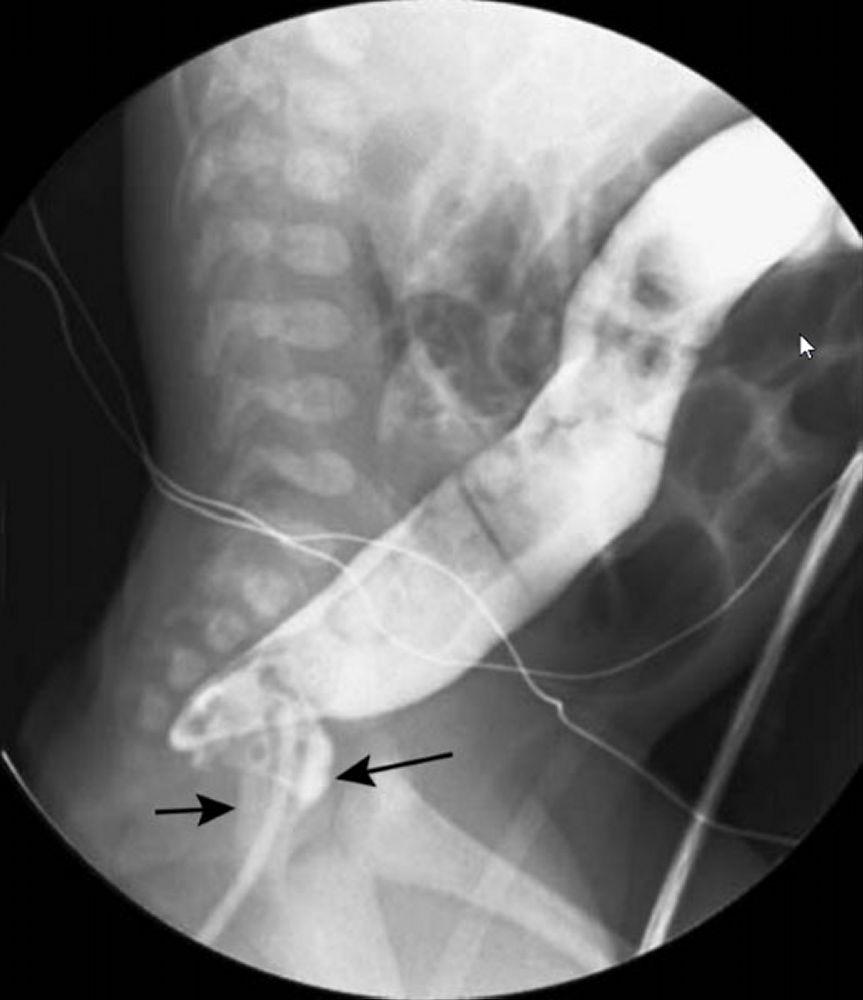

• Hirschsprung disease

• Failure to pass meconium, abdominal distension

• Due to absence of ganglion cells in distal colon

• Annular pancreas

• Can cause duodenal obstruction